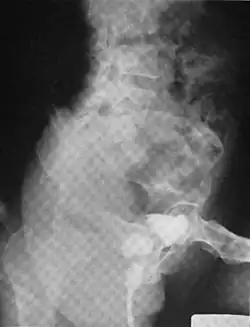

A urethral diverticulum seen on urethrogram

Another view of a urethral diverticulum seen on urethrogram

Urethral diverticulum is often an incidental finding.[2] It can be diagnosed using magnetic resonance imaging and/or micturating cystourethrography.[1] Other studies that can be used to diagnose urethral diverticulum include intravenous urography, urethroscopy, and/or ultrasound. Conditions that should be distinguished from urethral diverticulum in a differential diagnosis include overactive bladder, Gartner's duct cyst, Gartner's duct abscess, ectopic caeco-ureterocele, interstitial cystitis, pelvic inflammatory disease, endometriosis, and cancer.[3]